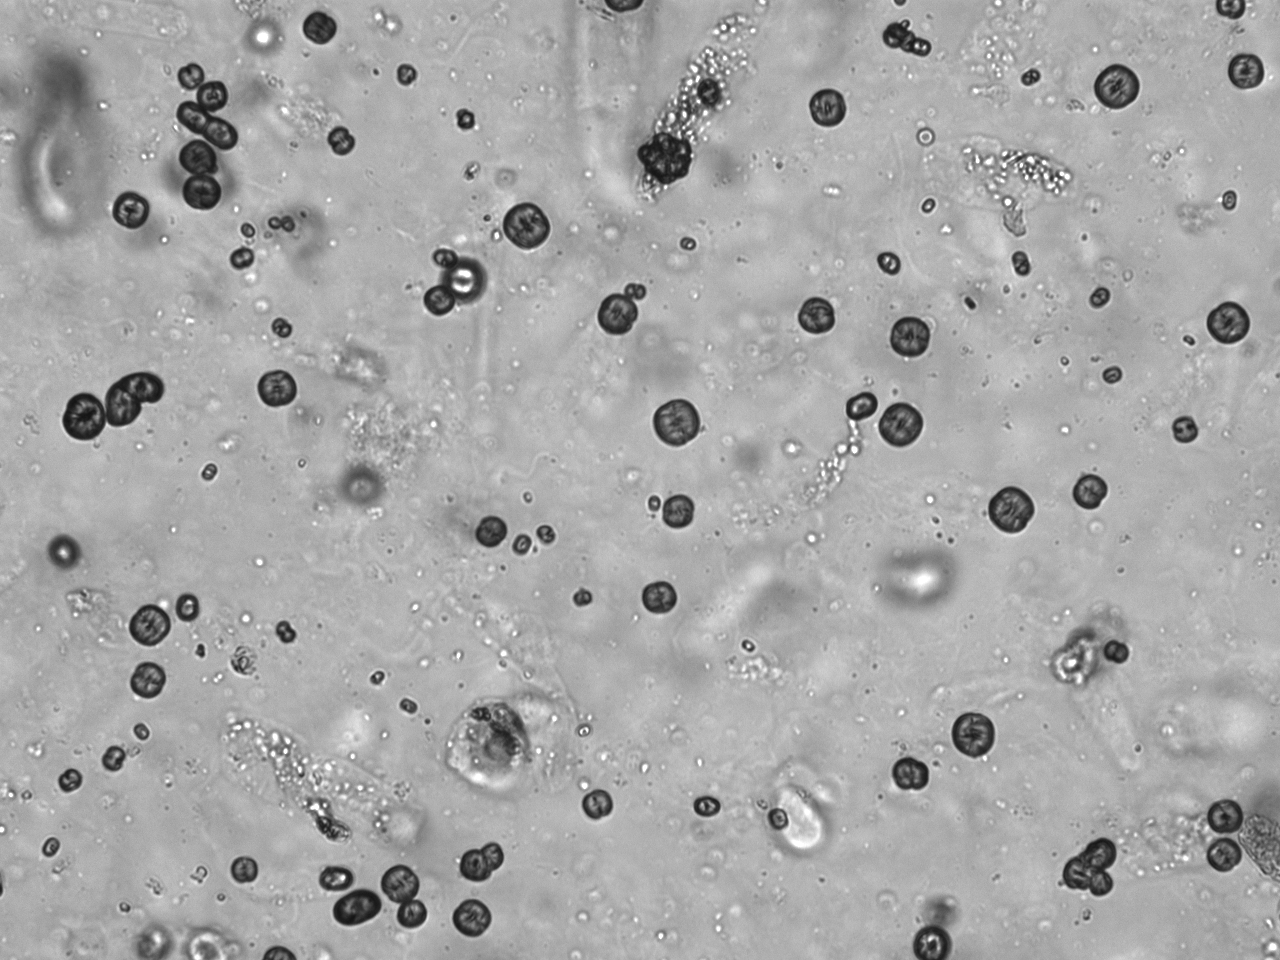

Urin-Feature: Leucinkugeln